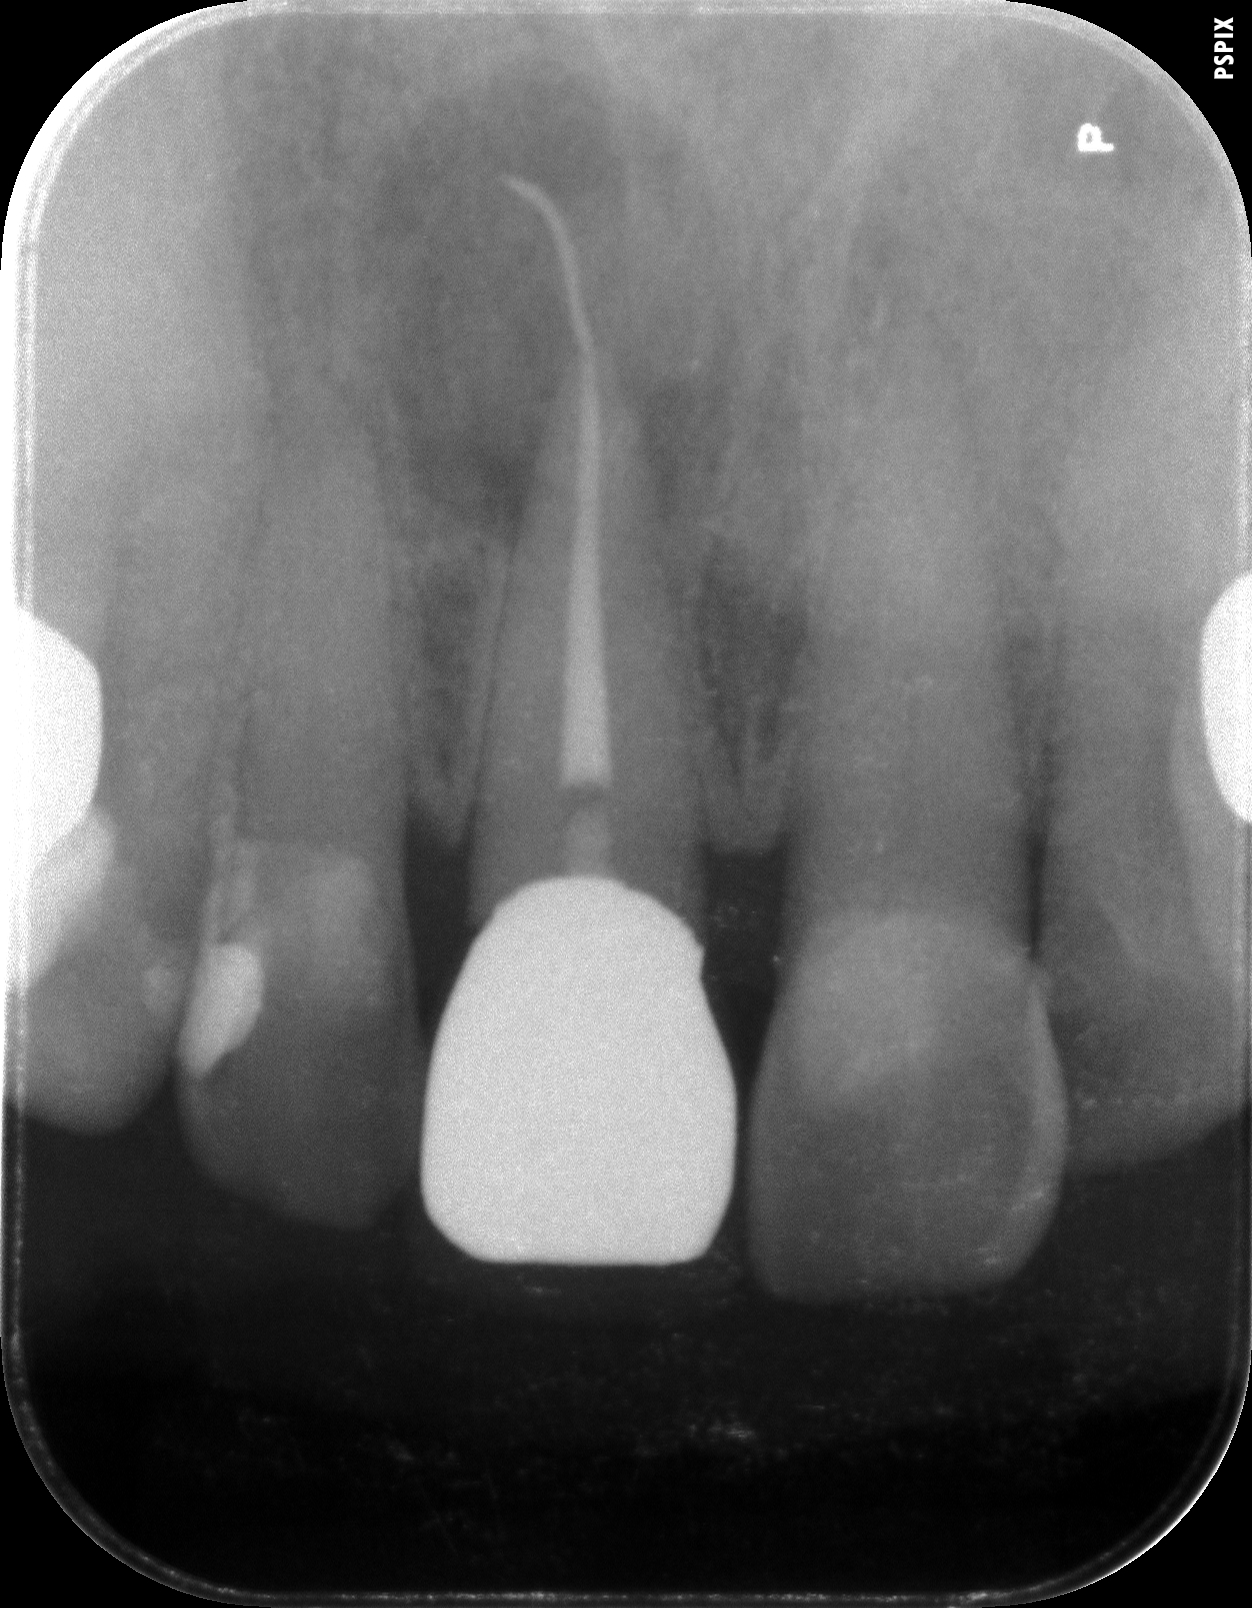

術前のレントゲン写真です。根の先の周りに黒い像がありますが骨の吸収像です。